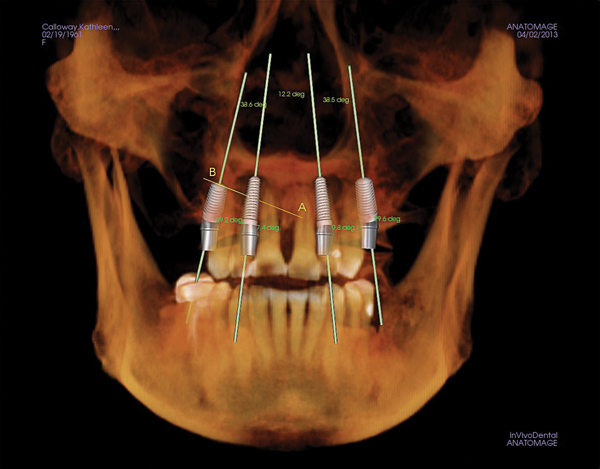

Figure 1 Traditional intraoral bitewing showing limited field of view (Fig 1) compared to the expanded view possible using CBCT (Fig 2).

Figure 1

Figure 2 Traditional intraoral bitewing showing limited field of view (Fig 1) compared to the expanded view possible using CBCT (Fig 2).

Figure 2

CBCT can also be used in this same manner to perform an even more common task, bitewing images, which are clinically indicated as often as every 18 to 24 months. For hygiene patients whose films require updating, CBCT offers a “patient-friendly” approach. Given that these films, which are usually performed intraorally, are often taken on an hourly basis in the typical general practice, the technology can be well utilized while also increasing comfort and satisfaction among patients. In addition, due to the expanded field of view that can be achieved with these extraoral CBCT images, they can often be more diagnostically valuable than images produced with an intraoral sensor (Figure 1 and Figure 2).